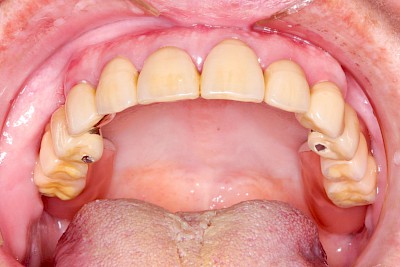

Wenn viele oder alle Zähne fehlen, können allein mit Brücken die Lücken nicht geschlossen werden. In diesen Fällen sind herausnehmbare Zahnprothesen notwendig. Ob Kronen, Brücke oder Prothesen – alle Arten von Zahnersatz haben das Ziel, dass wir gut kauen, gut und verständlich sprechen und ohne Scham herzlich Lachen und am Leben in der Gemeinschaft teilhaben können.

Teilprothese

Teilprothesen sind eine Möglichkeit, Zahnlücken mit einer herausnehmbaren Prothese zu ersetzen.

Eine Sonderform der Teilprothese ist die sogenannte abnehmbare Brücke. Hier kann aufgrund der Zahl und günstigen Verteilung der Restzähne auf rosafarbenen Kunststoff verzichtet werden. Diese Teilprothesen haben einen sehr hohen Tragekomfort und fallen zunächst nicht als herausnehmbarer Zahnersatz auf.

Beispiele mit Klammern 50 Bilder

Beispiele mit Geschieben 47 Bilder

Beispiele mit Teleskopen (Doppelkronen) 124 Bilder